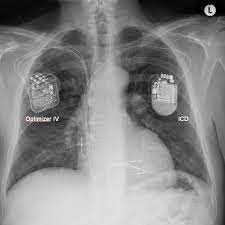

Device implantable inside the body, able to perform cardioversion, defibrillation, and (in modern versions) pacing of the heart. Llll aktueller und unabhängiger defibrillator test bzw. Während der programmierung haben wir ein kleines grafikdienstprogramm, das die zeit misst und anzeigt, während das gerät programmiert wird. Der internal cardiac defibrillator (icd) schützt patienten vor der todesursache nummer eins: It contains codes for diseases, signs and symptoms, abnormal findings, complaints, social circumstances, and external causes of injury or diseases.

My laptop is inspiron 5567, and i am using windows 10 operating system. Ein icd wird per se erst aktiviert, wenn er eine lebensbedrohliche arrhythmie erkennt. Es wird unter der haut im bereich des oberen brustkorbs (oder manchmal im bereich des bauches) implantiert. Seit etwa 30 jahren existiert der defibrillator als implantat, ähnlich einem herzschrittmacher. Der internal cardiac defibrillator (icd) schützt patienten vor der todesursache nummer eins: Erkennt das gerät eine solche rhythmusstörung, könne es durch eine sog. Llll aktueller und unabhängiger defibrillator test bzw. Es besteht aus einem aggregat, das die batterie und den elektronischen schaltkreis beinhaltet, und den elektroden, die die impulse zwischen dem herzen und dem aggregat hin und her leiten. Ein icd wird in eine person implantiert, hauptsächlich, um zu verhindern, dass er / sie aufgrund von kammerflimmern plötzlich stirbt. Technological advances and increasing operator experience have improved the success rate of transvenous lead extraction (tle). Der defibrillator erkennt über ein elektrogramm einen schnellen und lebensbedrohlichen herzrhythmus. Im gespräch mit medscape deutschland erläuterte prof. When i go to device manager, i found that i2c hid device is not working well.

Ein icd wird in eine person implantiert, hauptsächlich, um zu verhindern, dass er / sie aufgrund von kammerflimmern plötzlich stirbt.

Es besteht aus einem aggregat, das die batterie und den elektronischen schaltkreis beinhaltet, und den elektroden, die die impulse zwischen dem herzen und dem aggregat hin und her leiten. It shows the device cannot start (code 10) in properties. Es wird unter der haut im bereich des oberen brustkorbs (oder manchmal im bereich des bauches) implantiert. It contains codes for diseases, signs and symptoms, abnormal findings, complaints, social circumstances, and external causes of injury or diseases. Llll aktueller und unabhängiger defibrillator test bzw.